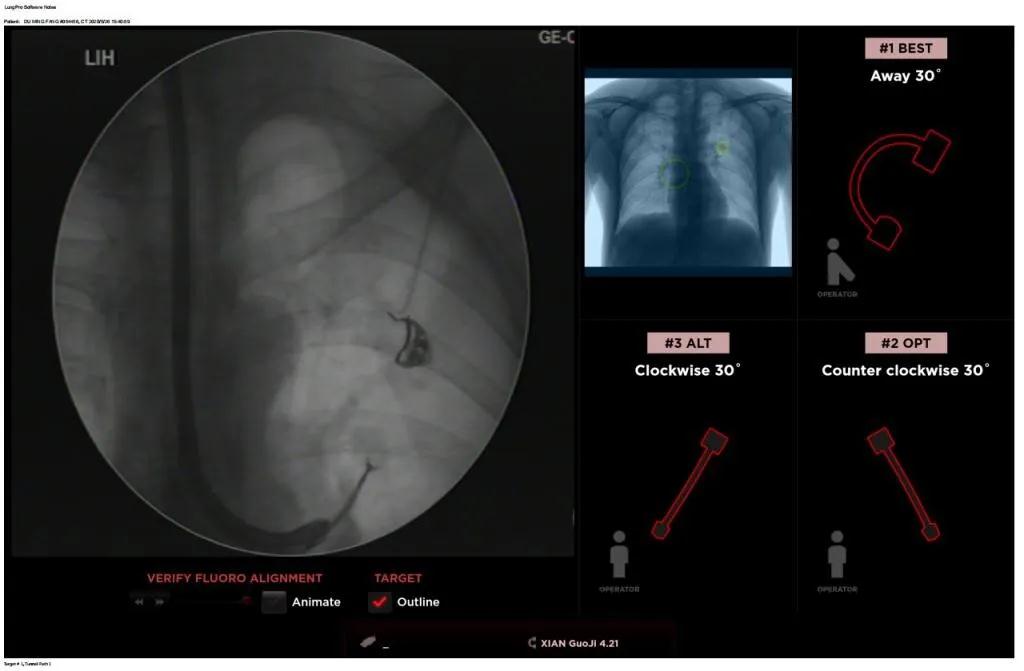

西安國際醫(yī)學(xué)中心醫(yī)院呼吸內(nèi)科完成西北地區(qū)首例LungPro全肺導(dǎo)航系統(tǒng)引導(dǎo)下BTPNA手術(shù)

近日,西安國際醫(yī)學(xué)中心醫(yī)院胸科醫(yī)院歐陽海峰副院長完成西北地區(qū)首例LungPro全肺導(dǎo)航系統(tǒng)引導(dǎo)下經(jīng)支氣管鏡跨肺實(shí)質(zhì)肺外周結(jié)節(jié)活檢術(shù)。

經(jīng)過充分的討論后,歐陽海峰副院長決定為患者實(shí)施LungPro全肺導(dǎo)航系統(tǒng)引導(dǎo)的經(jīng)支氣管跨肺實(shí)質(zhì)肺外周結(jié)節(jié)活檢術(shù)。Broncus導(dǎo)航系統(tǒng)LungPro具有全球領(lǐng)先獨(dú)創(chuàng)的BTPNA技術(shù)(支氣管鏡下跨結(jié)節(jié)抵達(dá)術(shù)),可以實(shí)現(xiàn)對氣道外周孤立性肺小結(jié)節(jié)的精準(zhǔn)定位,建立直接通往氣道外病變部位的通道,以實(shí)現(xiàn)全肺的診斷及后續(xù)治療。這項(xiàng)技術(shù)不僅彌補(bǔ)了現(xiàn)有支氣管鏡技術(shù)由于受限于病變部位是否有氣道可通向以及無法準(zhǔn)確定位病變部位而造成的較低診斷率,同時還彌補(bǔ)了CT引導(dǎo)下經(jīng)胸穿刺(TTNA)無法適用于某些特定部位如中央及肩胛骨等結(jié)節(jié)的問題,并且還避免了經(jīng)胸穿刺給患者帶來氣胸、出血的高風(fēng)險(xiǎn),可有效提高肺部結(jié)節(jié)及早期肺癌診斷陽性率,亦可用于早期肺癌的射頻消融或微波治療,具有微創(chuàng)、安全、同期雙肺診療等優(yōu)勢。

團(tuán)隊(duì)術(shù)前進(jìn)行了精心的準(zhǔn)備,通過高分辨率CT建立了導(dǎo)航路徑,在麻醉科手術(shù)室的配合下,借助LungPro引導(dǎo)順利的確定了病灶部位、建立隧道并實(shí)施活檢,術(shù)后患者恢復(fù)順利出院。